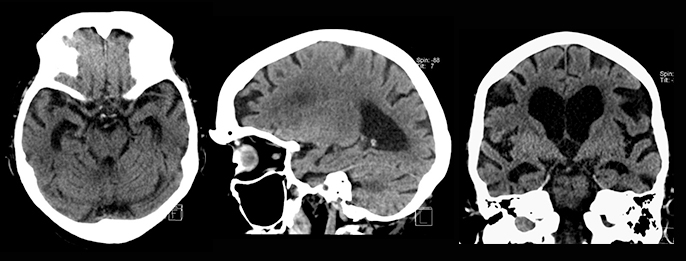

Muistipotilaan rutiinikuvausprotokolla tietokonetomografiassa (Muisti-TT)

Muistihäiriöpotilaan TT-kuvaus tulisi tehdä 3-dimensionaalisella muistiohjelmalla, joka parantaa menetelmän tarkkuutta. Viistokoronaali- ja sagittaalisuunnan reformaattikuvista voidaan arvioida suhteellisen luotettavasti kortikaalista ja temporomesiaalista atrofiaa sekä asteeltaan merkittäviä valkean aineen vaskulaarimuutoksia.